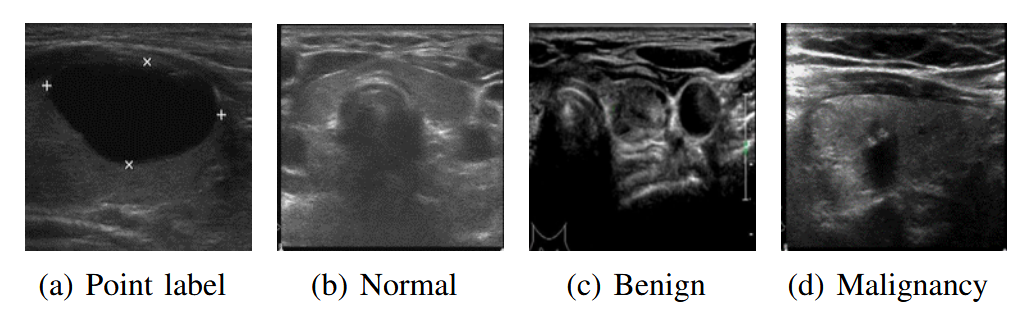

该方法通过修复病变数据中的病灶来增强正常数据,并通过**条件类别敏感策略(Conditional Category-Sensitive Strategy)**缓解病变数据之间的不平衡。整个过程仅使用图像级标注和病灶的点标注(医生在超声检查中用于测量病灶大小的标注,如图2(a)所示)。

本文中的甲状腺超声图像数据采集自天津医科大学肿瘤医院,包括8232张良性图像(BI,图2©)、9966张恶性图像(MI,图2(d))和404张正常图像(NI,图2(b)),均由专业影像医师标注。